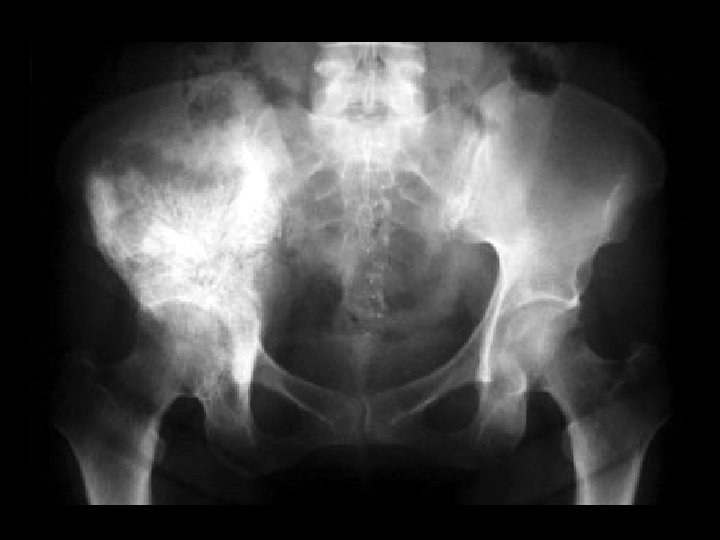

Fibrous dysplasia • Findings: – Mixed sclerotic and lytic lesion of the left hemipelvis and proximal femur – “shepherd's crook sign” • ddx: – NONE! – This is an Aunt Minnie!